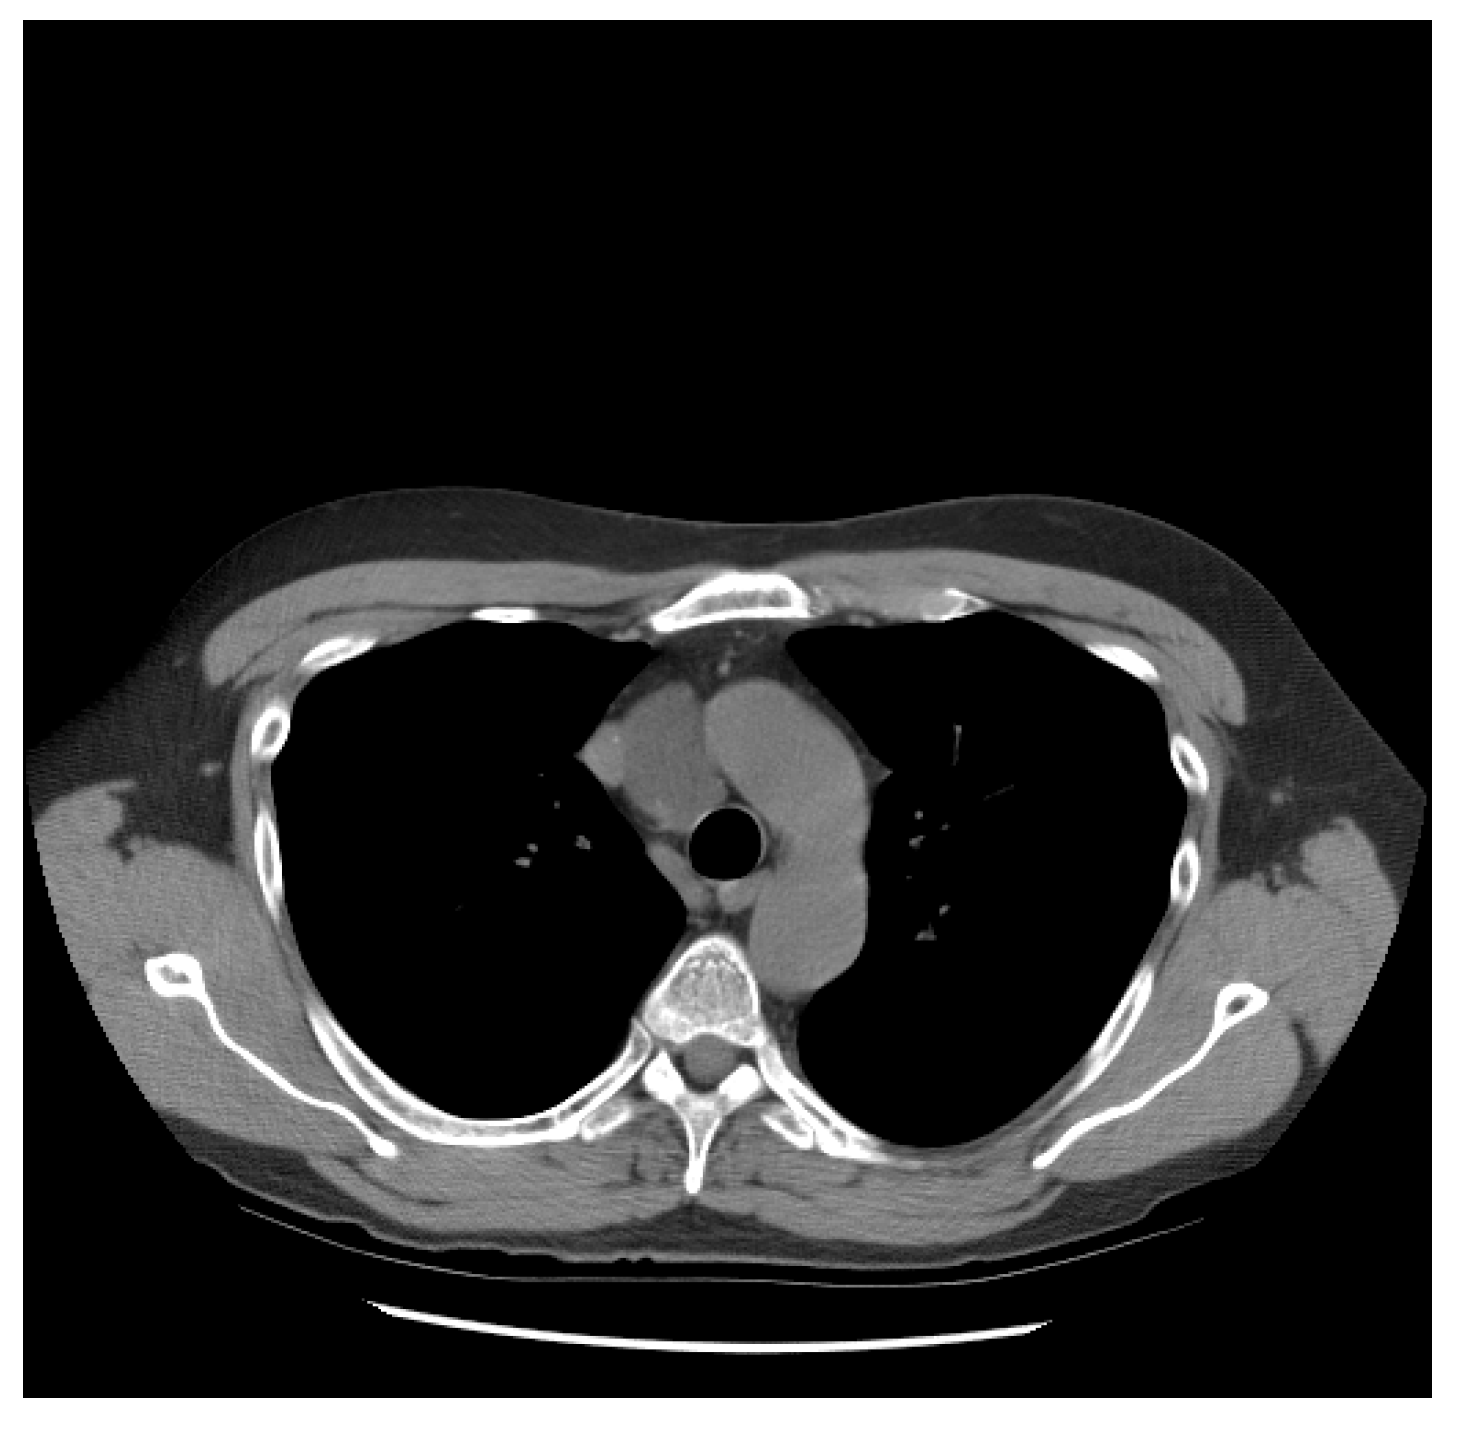

| Patient NSGCT Type | Status | Pathology of Primary | Stage at Time of Diagnosis | S-YSTemic Chemo | Date: Pathology after Chemo |

|---|---|---|---|---|---|

| 1 ETT | Cured | 100% S (elevated AFP) | IIX | BEP x1, VIP x3, paclitaxel (docetaxel), doxorubicin, gemcitabine, | 6/2012: 90% T, 10% ETT + adenocarcinoma |

| 2 S-YST | Cured | 5% E, 90% S, 5% Y | IIIC | BEP x4 | 5/2018, 4/2019, 4/2020: 99% S-YST + 1% T |

| 3 ETT | Cured | 80% ETT, 20% T | IIC | BEP x3 | 1/2018: T w/minute ETT |

| 4 S-YST | Died | NA Y in met | IIIC | BEP x4 | 9/2016: T 1/2021: S-YST |

| 5 ETT | Died | 100% E | IIIA | BEP x1, EP x3, TIP x4, POMB x2, ATP x4, TIP x1/HDC + SCT | 7/2019: Embryonal 11/2019: ETT 1/2020: Choriocarcinoma |

| 6. ETT | Died | 99% E, 1% T | IIIA | BEP x3, TIP x3, ATP | 9/2018: E, C 7/2019, 8/2019: 60% ETT + squamous cell carcinoma |

| 7 S-YST | Died | NA i(12p)+ in met | IIC | BEP x2, XELOX, ATP x2 | 8/2019: S-YST (Unresectable) |